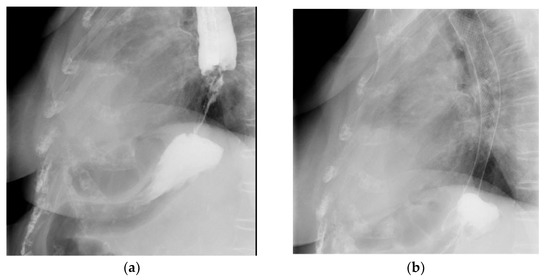

2.6. Enteral Stents